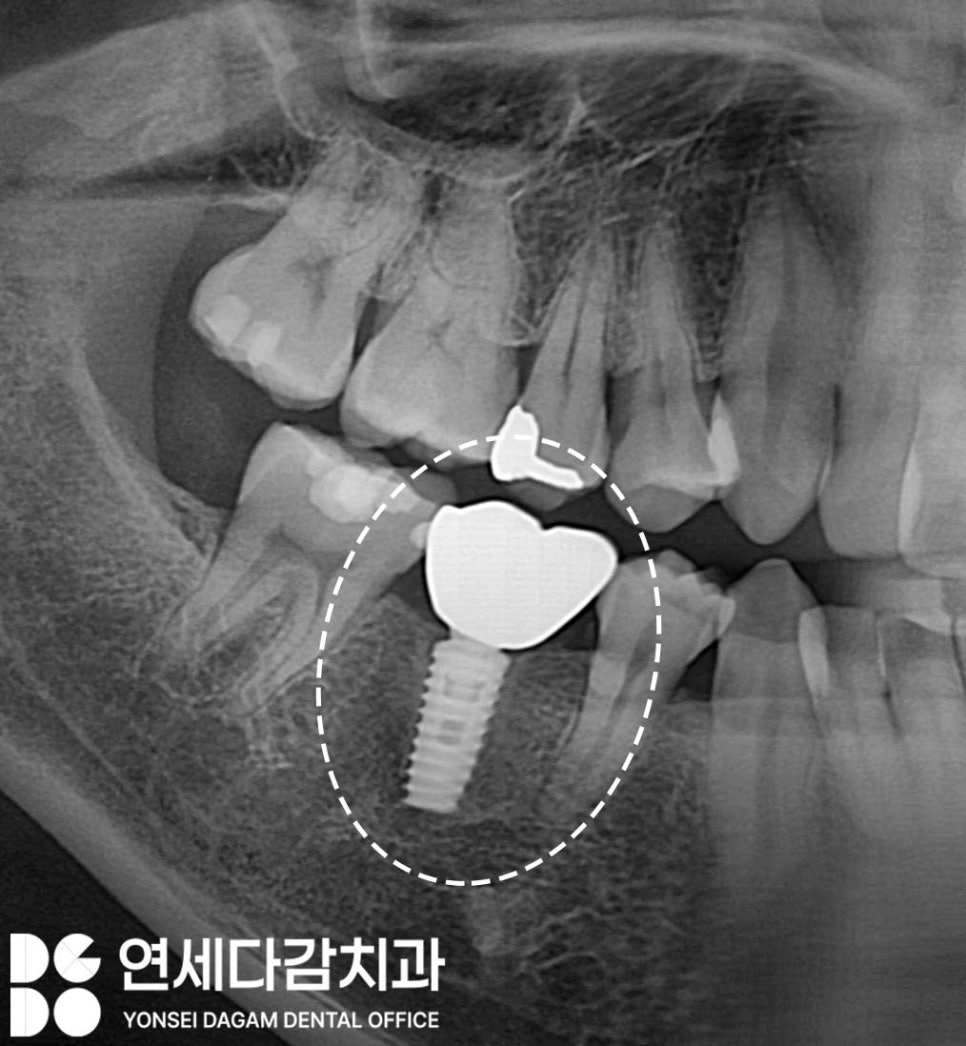

만약 고정체(fixture)와 어버트먼트를

연결하는 보철 나사(screw)가

부러지게 된다면,

임플란트 상부 구조물이

흔들리고 빠지게 됩니다.

이 상태가 지속되면

교합이 정상보다 높아지는

과교합 상태가 되어

마모 또는 파절 같은

더 큰 문제를 일으킬 수 있습니다.

이후 새로운 보철물을 제작하여

기능을 회복할 수 있습니다.

이렇게 적절한 방법으로

접근한다면 재수술 없이도

해결할 수 있는 경우가 있습니다.

이러한 방법으로 해결되면

수술을 하지 않아

전체 치료 기간 및

비용 부담도 크게 줄일 수 있게 된 겁니다.